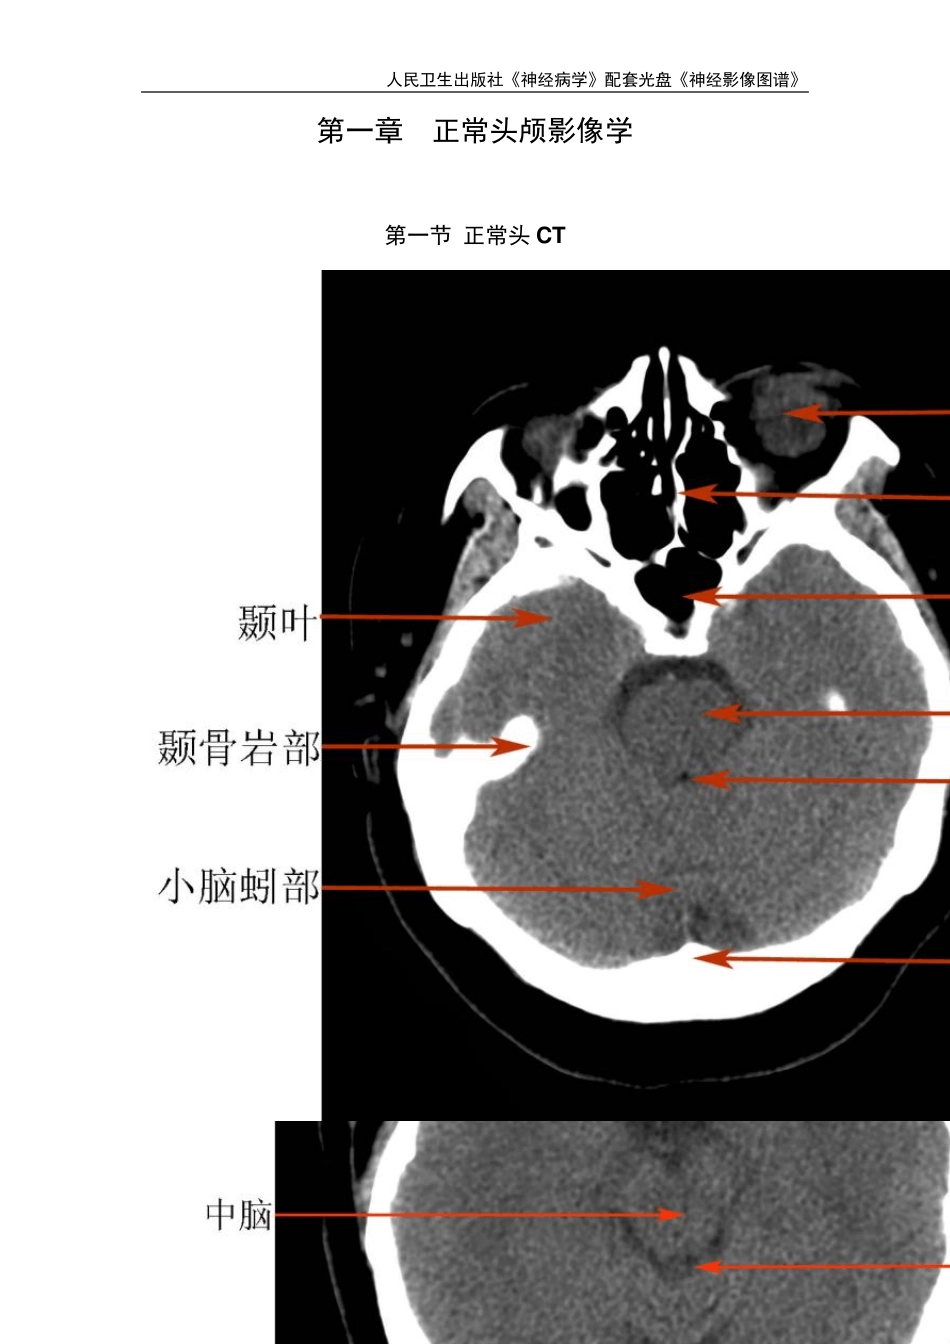

人民卫生出版社《神经病学》配套光盘《神经影像图谱》 人民卫生出版社《神经病学》配套光盘《神经影像图谱》 第一章 正常头颅影像学 第一节 正常头 CT 人民卫生出版社《神经病学》配套光盘《神经影像图谱》 人民卫生出版社《神经病学》配套光盘《神经影像图谱》 人民卫生出版社《神经病学》配套光盘《神经影像图谱》 第二节 正常头 MR 人民卫生出版社《神经病学》配套光盘《神经影像图谱》 人民卫生出版社《神经病学》配套光盘《神经影像图谱》 人民卫生出版社《神经病学》配套光盘《神经影像图谱》 人民卫生出版社《神经病学》配套光盘《神经影像图谱》 人民卫生出版社《神经病学》配套光盘《神经影像图谱》 人民卫生出版社《神经病学》配套光盘《神经影像图谱》 人民卫生出版社《神经病学》配套光盘《神经影像图谱》 第三节 正常 CTA 、人民卫生出版社《神经病学》配套光盘《神经影像图谱》 人民卫生出版社《神经病学》配套光盘《神经影像图谱》 第四节 正常 MRA 人民卫生出版社《神经病学》配套光盘《神经影像图谱》 第二章 脑血管病 第一节 脑梗塞 左侧额颞叶、基底节区超急性期脑梗死,发病 2 小时,T1WI、T2WI 及 flair 像未见异常信号,DWI 见高信号,ADC 图为低信号,MRA 示左侧大脑中动脉闭塞,右侧大脑中动脉狭窄。 人民卫生出版社《神经病学》配套光盘《神经影像图谱》 左侧基底节区急性期脑梗死,发病24 小时,T1WI 为稍低信号,T2WI 及flair 像为稍高信号,DWI 为高信号,MRA 示左侧大脑中动脉闭塞,此时头CT 未见异常改变。 人民卫生出版社《神经病学》配套光盘《神经影像图谱》 左侧基底节区亚急性期脑梗死,发病7 天,T1WI 为稍低信号,T2WI 及flair 像为高信号,DWI 为高信号,ADC 图为等信号,MRA 示左侧大脑中动脉闭塞。 人民卫生出版社《神经病学》配套光盘《神经影像图谱》 右侧基底节区多发腔隙性脑梗塞形成软化灶,周围见胶质细胞增生。 人民卫生出版社《神经病学》配套光盘《神经影像图谱》 皮层下动脉硬化性脑病,脑萎缩脑沟增宽加深脑室增大,双侧放射冠多发腔隙性脑梗塞部分已软化,双侧脑室周围对称性条带状异常信号。 人民卫生出版社《神经病学》配套光盘《神经影像图谱》 脑桥梗塞,发病3 天,T1WI 为稍低信号,T2WI 及flair 像为高信号,DWI 为高信号。 人民卫生出版社《神经病学》配套光盘《神经影像图谱》 右侧小脑梗塞,发病3 天,T1...